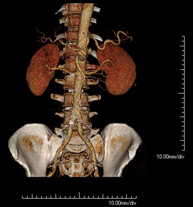

- Angio-TC arterias renales  Prueba diagnóstica no invasiva que consiste en el estudio de las arterias renales obteniendo imágenes de alta definición anatómica mediante el empleo de un equipo de TC (Tomografía Computarizada) y de contraste yodado. La calidad de las imágenes permite realizar reconstrucciones en 2D y 3D gracias a estaciones de trabajo especializadas en el estudio arterial. Esta prueba está indicada, por ejemplo, en aquellos pacientes que sufren de HTA refractaria al tratamiento, en pacientes con lesiones renales para tener un mapa "vascular" pre-quirúrgico, etc. Prueba diagnóstica no invasiva que consiste en el estudio de las arterias renales obteniendo imágenes de alta definición anatómica mediante el empleo de un equipo de TC (Tomografía Computarizada) y de contraste yodado. La calidad de las imágenes permite realizar reconstrucciones en 2D y 3D gracias a estaciones de trabajo especializadas en el estudio arterial. Esta prueba está indicada, por ejemplo, en aquellos pacientes que sufren de HTA refractaria al tratamiento, en pacientes con lesiones renales para tener un mapa "vascular" pre-quirúrgico, etc.

- Angio TC d'artèries renals Prova diagnòstica no invasiva que consisteix en l'estudi de les artèries renals amb l'obtenció d'imatges d'alta definició anatòmica mitjançant l'ús d'un equip de TC (Tomografia Computaritzada) i contrast iodat. La qualitat de les imatges permet realitzar reconstruccions en 2D i 3D gràcies a estacions de treball especialitzades en l'estudi arterial. Aquesta prova està indicat en aquells pacients que pateixen HTA refractària al tractament, en pacients amb lesions renals que tenen un mapa vascular prequirúrgic, etc. Prova diagnòstica no invasiva que consisteix en l'estudi de les artèries renals amb l'obtenció d'imatges d'alta definició anatòmica mitjançant l'ús d'un equip de TC (Tomografia Computaritzada) i contrast iodat. La qualitat de les imatges permet realitzar reconstruccions en 2D i 3D gràcies a estacions de treball especialitzades en l'estudi arterial. Aquesta prova està indicat en aquells pacients que pateixen HTA refractària al tractament, en pacients amb lesions renals que tenen un mapa vascular prequirúrgic, etc.